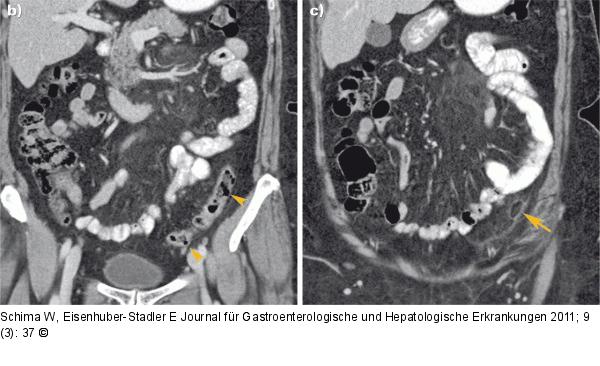

Abbildung 1b-c: MDCT Die koronalen MDCT-Rekonstruktionen zeigen anschaulich das Colon sigmoideum mit einzelnen Divertikeln (Pfeilspitzen), jedoch ohne Anzeichen einer Divertikulitis. Die entzündlichen Veränderungen sind auf die Appendix epiploica und das umgebende Fettgewebe beschränkt (Pfeil). |